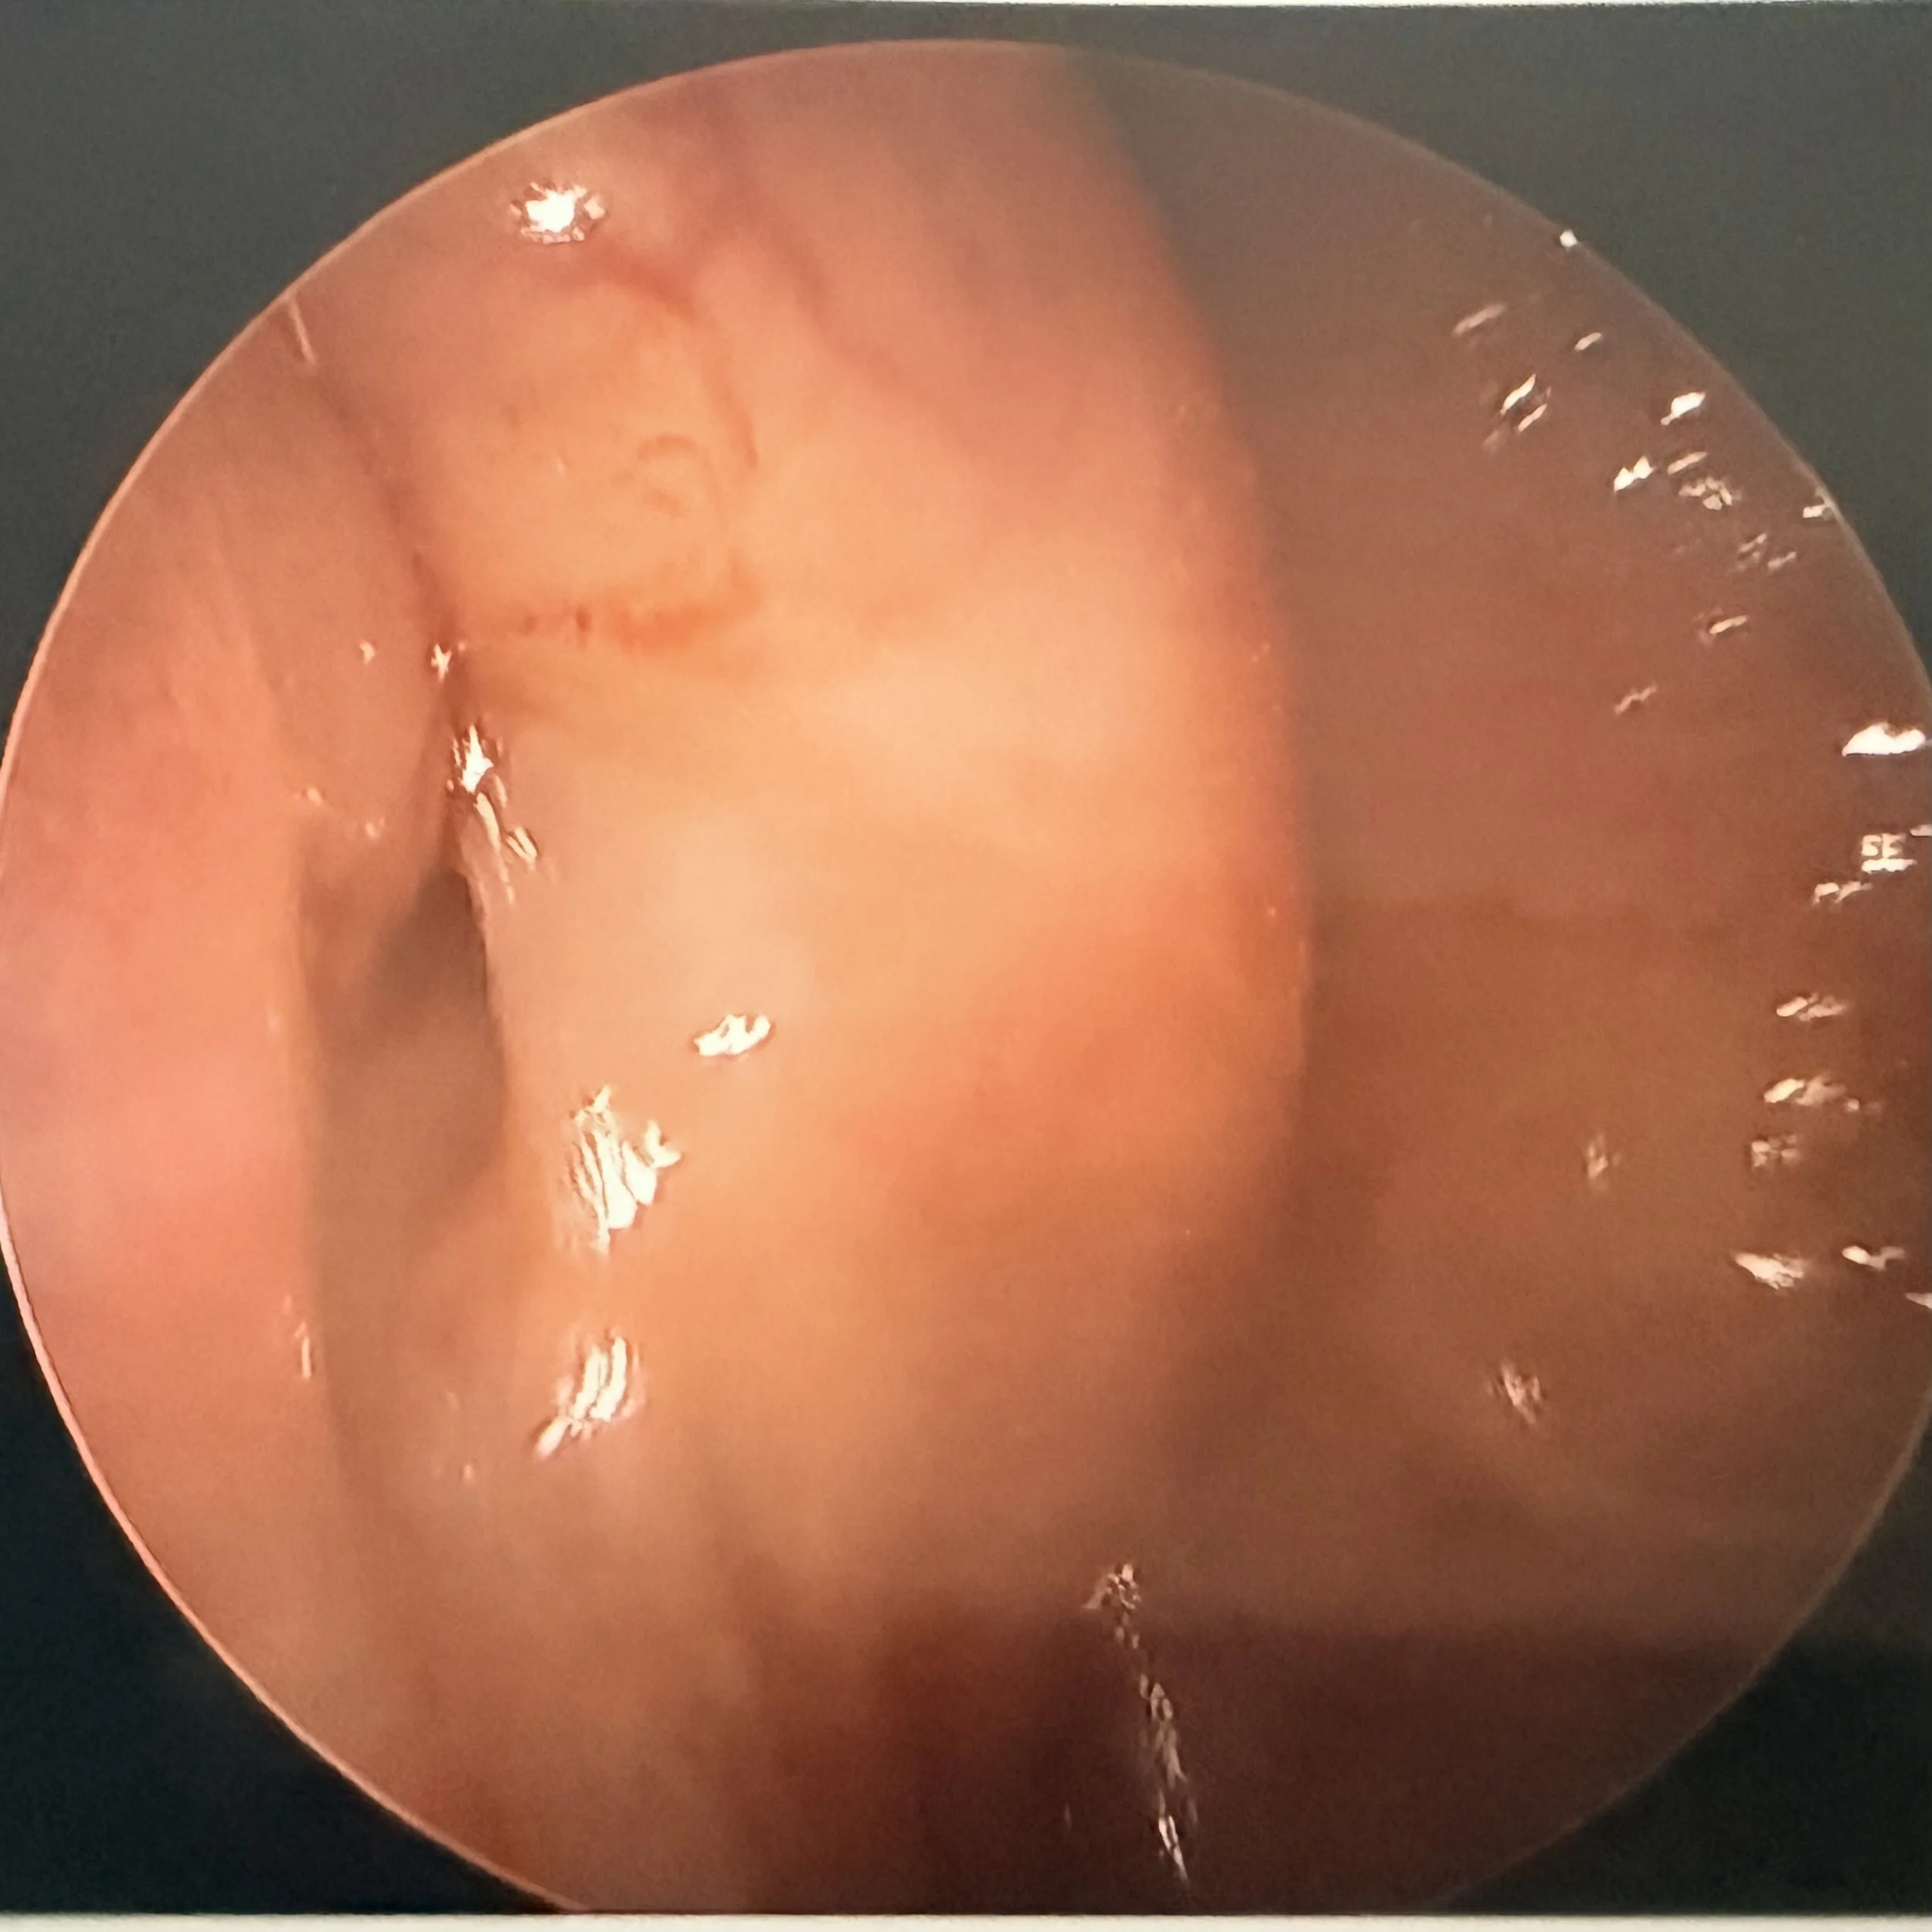

After Surgery

Endoscopic view of a closed eustachian tube following surgery

Primary Result: The image demonstrates successful mucosal coaptation (closure) of the Eustachian tube orifice, indicating the restoration of the anatomical valve seal at rest.

Anatomical Characteristics:

• Obliteration of Defect: The previously noted patent lumen or longitudinal cleft is no longer visible. The anterior tubal wall and the posterior cartilaginous cushion (torus tubarius) are now in direct apposition.

• Tissue Volume/Augmentation: The mucosa and underlying structures appear fuller or more voluminized compared to a typical patulous state. This increased tissue bulk is consistent with surgical intervention such as an injectable filler or cartilage graft, aimed at plumping the area to close the defect.

In short, this image shows a structurally successful surgical outcome, with the resting "keyhole" defect physically closed.